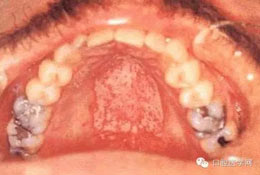

(一)念珠菌病

2.增生型: 為堅(jiān)固而致密的白色斑塊或針頭大小的小結(jié)節(jié),附著于紅色病變區(qū)。

3.偽膜型: 為白色或黃色可除去的斑點(diǎn)或斑塊。

(六) Kaposi肉瘤: 主要發(fā)生于軟、硬腭粘膜。